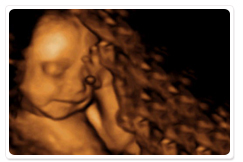

3D超音波検査を採用

3D超音波とは、お腹のなかのベビーを画像に映し出す超音波です。

通常の超音波画像とは違い、ベビーのお顔の表情やしぐさを見ることができます。(20分位)